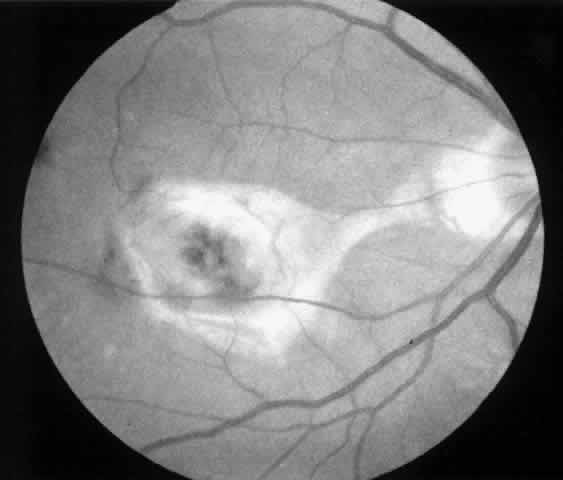

4. A 71-year-old patient with ARMD developed a recurrent choroidal neovascular membrane extending into the fovea with a preoperative vision of 20/320 (6/96) (Fig. 13). He had only marginal visual improvement after surgery (20/200 [6/60]) owing to a subfoveal RPE defect, but the size of the scotoma decreased after resolution of subretinal fluid (Fig. 14).

Fig. 13. Preoperative fluorescein angiogram (A) and Amsler grid (B) of a 71-year-old patient with age-related macular degeneration (case 4).